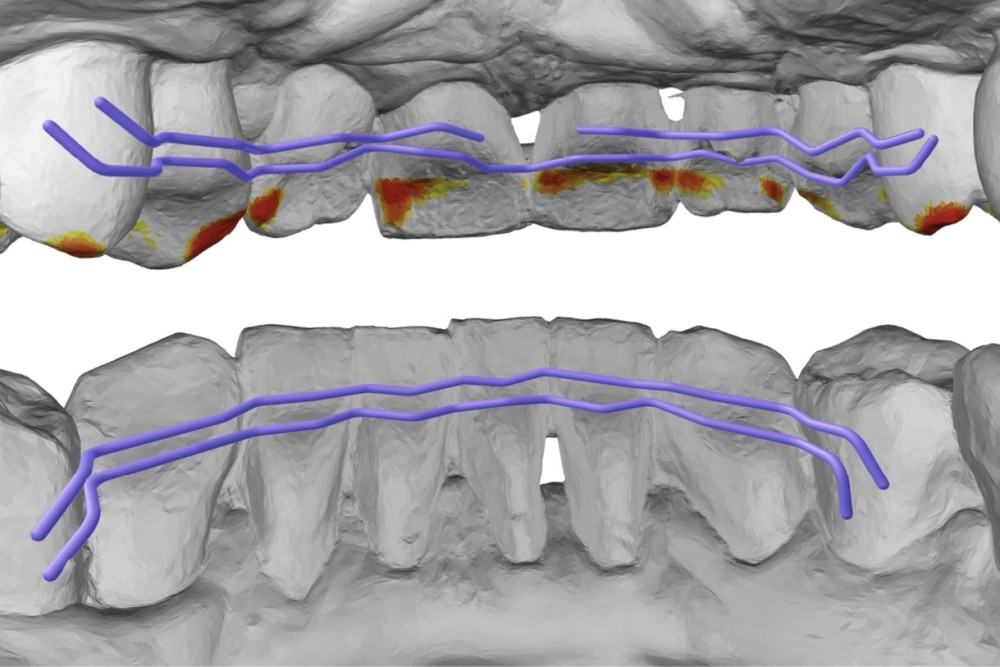

En raison de l’ancrage dentaire postérieur mandibulaire très limité, il est décidé d’utiliser des ancrages osseux pour l’ingression du bloc incisivo-canin mandibulaire, afin de niveler l’arcade et de recréer le surplomb nécessaire à la fermeture des diastèmes maxillaires. Deux minivis d’ancrage sont positionnées entre les dents 32/33 et 42/43, après réalisation d’un examen CBCT localisé sur l’arcade mandibulaire (fig. 7 et 8). Ces minivis antérieures ont été rapidement déposées, en raison de leur mobilité et de la gêne importante de la patiente liée au positionnement très apical du fait de l’alvéolyse.

Des minivis d’ancrage sont alors positionnées entre les dents 34/35 et 44/45 (fig. 9). Un sectionnel d’ingression antérieur (acier .018x.025) est fixé sur celles-ci, tout en passant par des tubes en croix situés entre les prémolaires afin d’éviter le dévissage des minivis. L’ingression est réalisée via des ligatures reliant l’arc orthodontique principal (TMA .018x.025 avec boucles double-delta) au sectionnel, selon une direction permettant l’ingression tout en limitant la composante de vestibulo-version. Du stripping mandibulaire a été réalisé de mésial de 33 à mésial de 43 afin de corriger l’indice de Bolton.